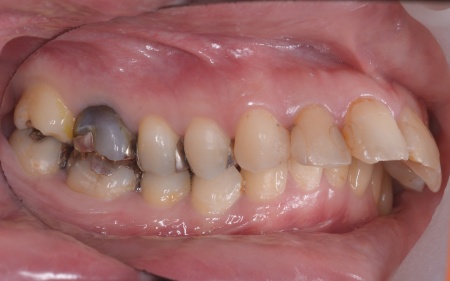

30代女性 出っ歯と開咬に対しアンカースクリューを用いたワイヤー矯正で治療した症例

拝見したところ、上前歯が大きく前に出ている上顎前突であり、上下の前歯が噛み合わずに口を閉じても前歯同士が接触しない「開咬(かいこう)」の状態でした。

また、前歯で食べ物をうまく噛み切ることができないため、奥歯にも強い負担がかかっているだけでなく、このまま放置すると、奥歯がすり減ったり痛みが生じたりするリスクもあります。

患者様の場合、骨格的な上顎前突が噛み合わせを乱している主な原因であることから、矯正治療では前歯を後方へ大きく動かすためのスペースを確保する必要があります。

上顎の奥歯(第1小臼歯)を左右1本ずつ抜き、奥歯にアンカースクリューを埋め込みます。上奥歯をしっかりと固定することで、抜歯で確保したスペースを最大限に活用しながら、前歯を効率よく後方へ牽引することが可能です。